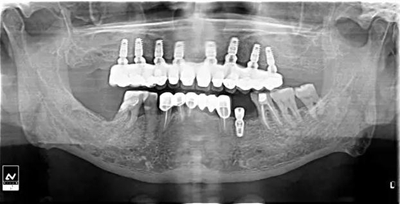

牙列缺失患者由于支持、固位、穩(wěn)定不足導致義齒效果差,如果在牙槽嵴內(nèi)植入種植體,種植體可以根據(jù)種植體數(shù)量不同提供義齒不同程度的固位、穩(wěn)定、支持,獲得不同的修復效果。當單頜牙列缺失患者使用1-2顆植體,植體和覆蓋義齒之間可以靠一些附著體如磁性附著體、桿卡式附著體、球帽式附著體等裝置連接,主要提供固位和穩(wěn)定作用,少量的支持作用,當單頜牙列缺失使用4顆植體時,很大部分支持力可以由植體承擔,當使用4顆以上植體時可完全由種植體提供義齒的支持、固位和穩(wěn)定,甚至制作為不可摘戴的全口固定種植義齒。

1、種植固定修復后,義齒的基托面積大大減小,從而大大提升了患者的舒適度,同時惡心、發(fā)音障礙也大大減輕;

2、種植固定修復采取的是種植體支撐,或者種植體+粘膜支撐的受力方式,咀嚼效率比全口義齒提升很多,通俗來講,也就是老年人基本可以正常進食,有利于老年生活的豐富和身體機能的保持;

3、種植固定修復因為有種植體的支撐,可以在一定程度上延緩牙槽骨的骨吸收,從而使義齒的使用年限更長;

當然,說到種植固定修復的缺點,除了可能出現(xiàn)的部分并發(fā)癥以外,不能不提的就是種植固定修復的價格,雖然遠沒到某教授講到的一口牙等于一輛寶馬那種情況,但總體金額比全口義齒確實要高很多。即使是種植固定修復也會有不同的修復方案,金額差距還是比較大的。